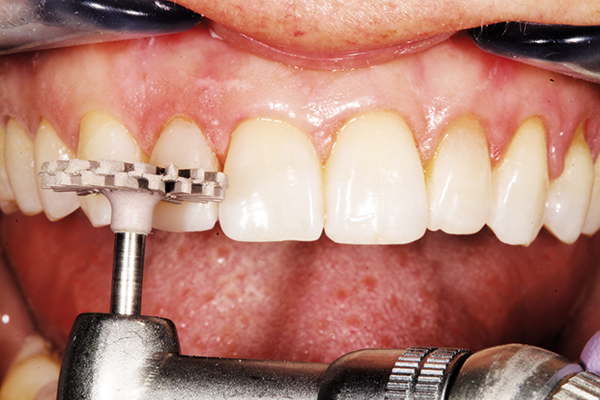

Smoothing the gingival margins and refining the primary anatomy was performed with a 12 fluted carbide ET9 finishing bur and coarse/fine composite finishing discs. Secondary anatomy was created with a fine diamond flame-shaped diamond to develop depressions between the three labial lobes. Occlusion was verified and adjusted with a 12 fluted egg-shaped bur (Fig. 10).

Fig. 10 Fig. 11

Interproximal polishing was done with various grits of strips to aid in flossing and to decrease the risk of stain buildup in the future (Fig. 11). ALPEN® ShapeGuard™ Composite Plus Step 2 Polishers and a felt polishing disc with aluminum oxide paste created a natural high gloss finish for esthetics and longevity (Fig. 12).